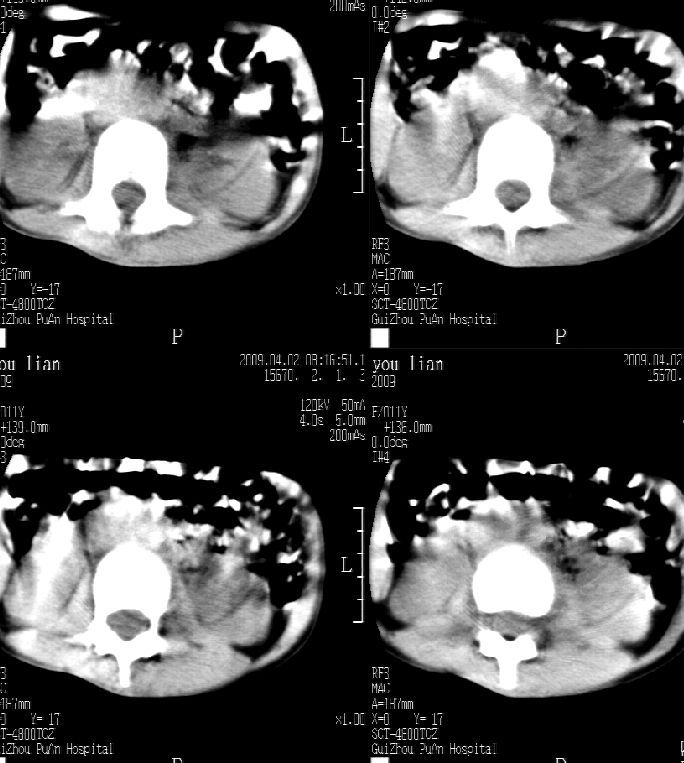

患儿女,11岁,因“腰痛,腰部活动受限10余天”入院。

10余天前,患儿无明诱因出现腰部疼痛,为持续性钝痛,以右侧为著,伴腰部活动受限,有发热,具体体温不详,无寒战、黄疸、盗汗、咳嗽,无尿频、尿急、肉眼血尿。

乍一看像是嗜酸性肉芽肿,但看到ct表现骨质破坏及软组织肿胀考虑结核可能性大,鉴别恶性肿瘤.

本例ct图像太不清楚了,而且不知道有没有传完,如果软组织病变只局限性于那几个层面的话多考虑嗜酸性肉芽肿,其次为其他肿瘤,结核椎旁软组织较广泛,在本例没有太典型表现,建议楼主(孩子父母吧)把所有的软组织窗图像(白色的那种)按顺序全部转上来.

考虑结核可能性大。

考虑l3嗜酸性肉芽肿。